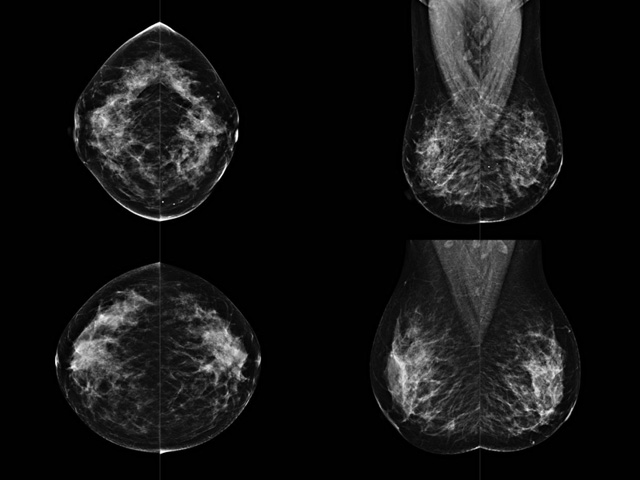

乳房檢查時候要注意一些細節(jié),需要更深入的了解這樣才能使檢查更準確。乳腺DR是乳腺癌的篩查診斷工具設備。是乳房方面檢查的重要影像方法。它可以臨床檢查出早期的乳腺癌??梢耘袛嗔夹詯盒?。因為它可以檢查出早期的病變。對良性惡性檢查的準確率達到90%以上。發(fā)病高峰年齡為45歲到54歲。50歲檢查出來乳腺癌病患,可以讓死亡率下降3成。所以30-40歲女性每年做一次乳腺DR檢查。40歲以上就一年兩次。如果家族史有乳腺癌的30歲以下也需要做檢查。清晰顯示乳腺各層組織嚴重的乳腺增生,乳腺炎,乳腺外傷也建議1年檢查一次。極大提高了早期乳腺癌的敏感度和診斷率。

大角度、高質(zhì)量的乳腺檢查,可以讓女性帶來身體健康安全。為醫(yī)生提供了高清影像數(shù)據(jù)。乳腺檢查時候各個部位影像顯示出來。白色乳腺導管跟纖維結締組織。模糊的是脂肪。病變一般是不透明的白色。有需要放大來檢查。乳腺DR沒有重疊偽影。輻射劑量更少。因為乳腺癌發(fā)病每年都有所提高,對女性都造成了嚴重的身體健康危害。早做檢查早治療是不可忽視的舉措??梢源蟠蟮慕档?/span>死亡率。保證身體健康。一般檢查避開經(jīng)期,來完7天左右是最佳的檢查時間。絕經(jīng)的女性就沒有要求。孕婦不參加乳腺DR檢查, 6個月內(nèi)準備妊娠的婦女也不宜行此檢查。